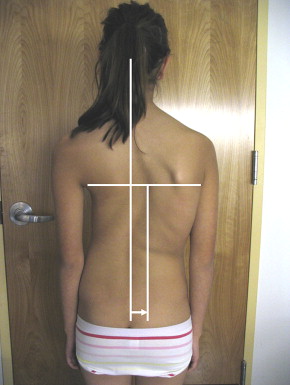

1. عدم تساوي الكتفين

إذا لاحظت أن أحد الكتفين أعلى من الآخر بشكل واضح، فقد يكون ذلك مؤشرًا على وجود انحناء في العمود الفقري.

3. ميل الجسم إلى جهة واحدة

إذا كان الطفل يقف أو يمشي وهو مائل إلى جانب معين، فقد يشير ذلك إلى وجود مشكلة في التوازن أو العمود الفقري.

4. اختلاف شكل الخصر أو القفص الصدري

اختلاف مستوى الخصر أو بروز أحد الجانبين أكثر من الآخر يشير إلى عدم التوازن العضلي أو وجود اعوجاج.

اختبار بسيط للأهل في المنزل لأكتشاف أي مشكلة في العمود الفقري

يمكنك عمل اختبار سريع:

- اطلب من الطفل الوقوف بشكل مستقيم.

- اجعله ينحني للأمام ببطء.

- راقب الظهر من الخلف.

إذا لاحظت:

- بروز في جهة واحدة

- عدم تماثل واضح

- اختلاف مستوى الجانبين

فمن الأفضل استشارة مختص في أقرب وقت.